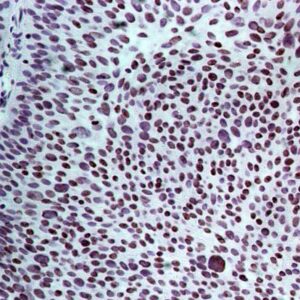

BioGenex has pioneered the development of miRNA research and diagnostics tools with leading-edge products. Currently, we offer over 240 ready-to-use (RTU) Super Sensitive™ Nucleic Acid (SSNA) miRNA ISH probes for accurate and early tumor diagnosis. These probes are sensitive enough to detect low-abundant miRNA(s) that are often required to identify biomarkers. They have a high melting temperature enabling stringent washes to remove non-specific binding. BioGenex miRNA probes are dual-end labeled with an anti-fluorophore to amplify the signal and yield clean and intense staining.